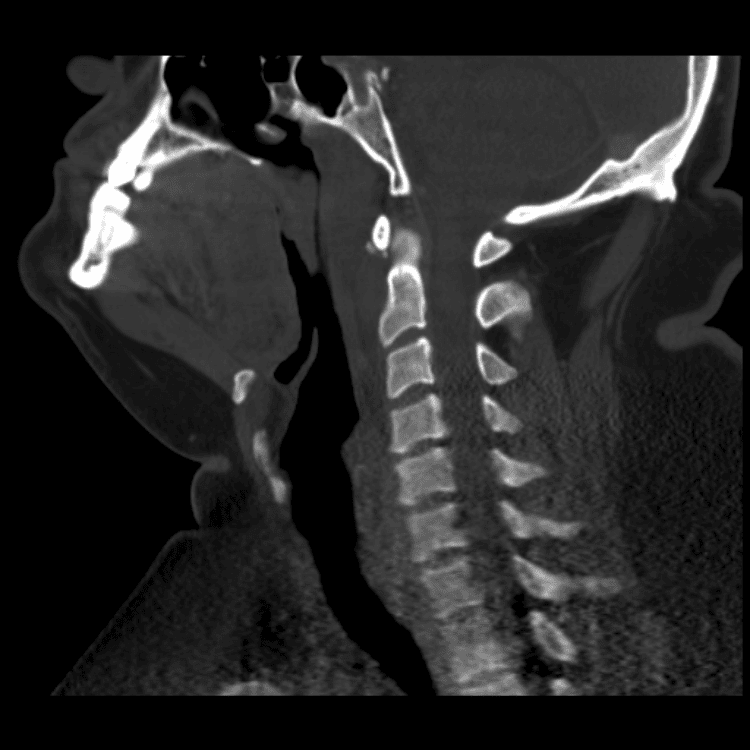

Head and Neck

Simulates call by including subtle or difficult cases and some normals.

27 cases